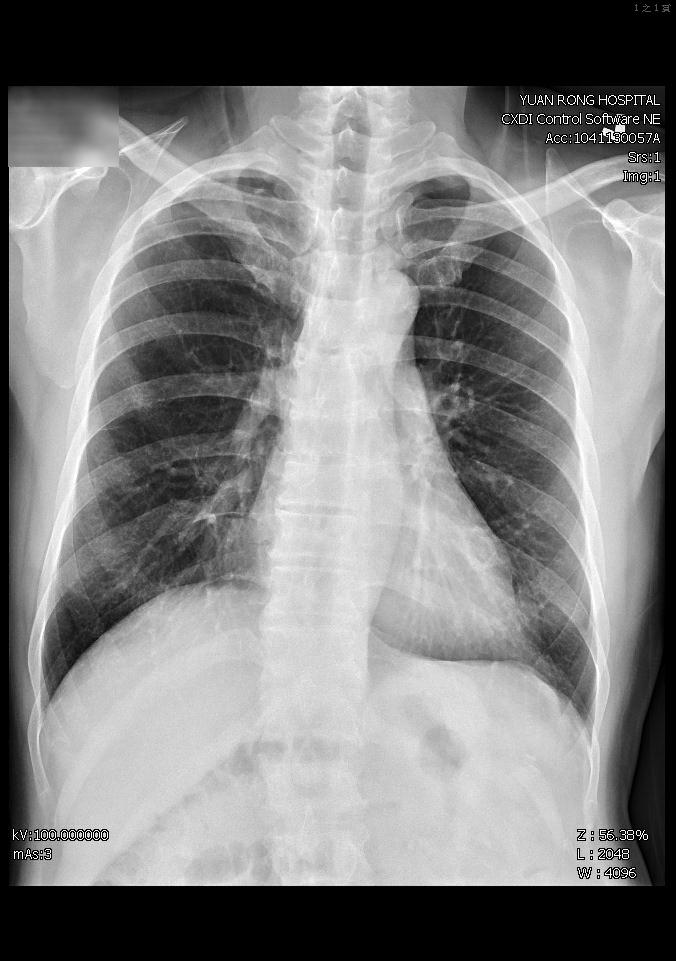

感染管制師李亦晨說,結核菌須在特殊培養基中才能培養出來,一般檢查需45天至60天,但這名台商在第24天就確定為膀胱結核,醫院依規定通報衛生局,並告知台商應連續服藥6個月,院方為他做肺部X光和痰液檢查,排除肺部感染,腎功能幸未受影響。